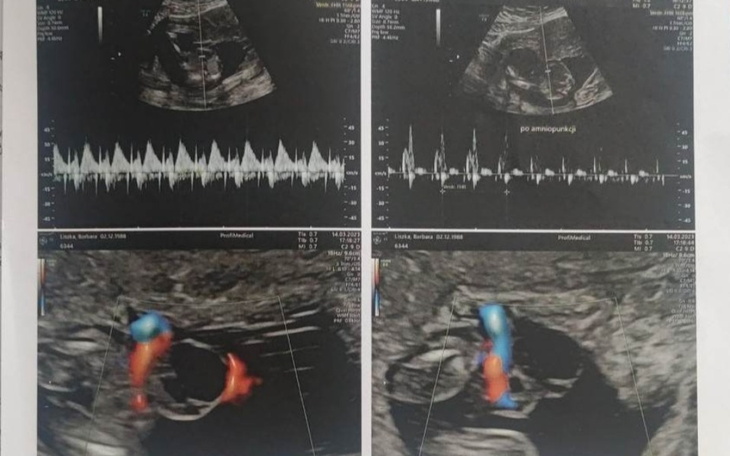

Stworzyłam zbiórkę dla Mojej Cioci która została z 3 dziedzi i kolejnym dzieckiem w brzuszku ....Niestety dzidziuś jest chory potrzebuje wizyt u specjalisty niestety jej nie stać na to :( Partner wyjechał i zostawił ją z tym wszystkim ..... Ciąża jest zagrożona potrzebuje pilnie jechać do kliniki lecz bez badań nic nie zrobi :( niema jak się tam dostać niema co zrobić z dziećmi :( a jej życie jest zagrożone :( do galerii dołączę zdjęcia badań które ma ,wynik aminopunkcji gdzie wskazuje że dzidziuś jest chory :( Dzwoni do mnie dziennie płacze do telefonu a ja jej nie pomogę bo niemam jak :( Dlatego pomyślałam o tej zbiórce :( 😭😭😭😭😭 Straszne że człowiek potrafi tak zostawić swoją ukochaną osobę i zostawić wszystkim tym bardziej że zagraża to jej życiu :(((((((( Proszę o udostępnienie mojej zbiórki liczy się czas ......Jutro miała być w klinice niema badań musi je zrobić w tym tyg a wszystko kosztuje ;( Bardzo wszystkim będę dziękowała za okazane wsparcie ..... Ale liczy się czas a bez pieniędzy nic nie zrobimy :( będziemy musieli czekać aż coś się stanie a tego raczej nikt niechce aby dzieci zostały bez matki :( Jej pieniądze idą na opłacenie mieszkania rachunków a na resztę już jej nie starcza pożycza od znajomych ale to niestety nie wystarcza a trzeba będzie to oddać :( Straszne jest to życie ale jeśli ktoś może to niech Jej pomoże 🙏🙏🙏🙏Będę bardzo wdzięczna 🙏❤️